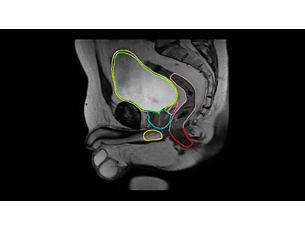

Whether for external beam radiation therapy (RT) or brachytherapy, integrating MR imaging into CT‑based planning can harness the power of MRI and transform patient management. With MRI’s excellent soft-tissue contrast, you can clearly see the tumor and organs at risk. So you can support accuracy in delineation and design the best possible treatment plans. Image courtesy of William Beaumont Health System, Detroit, USA - A superb MRI platform for radiation oncology

See clearly in treatment planning

Enjoy consistent, excellent image quality for multiple anatomies. Versatile arrangements of dStream coils work together with ExamCards tailored for RT to provide high-contrast images with high geometric fidelity. Quickly execute complete imaging protocols for prostate, female pelvis, brain, head and neck, and spine. - Learn and share MRI expertise

Whether for external beam radiation therapy (RT) or brachytherapy, integrating MR imaging into CT‑based planning can harness the power of MRI and transform patient management. With MRI’s excellent soft-tissue contrast, you can clearly see the tumor and organs at risk. So you can support accuracy in delineation and design the best possible treatment plans. Image courtesy of William Beaumont Health System, Detroit, USA - A superb MRI platform for radiation oncology

See clearly in treatment planning

Enjoy consistent, excellent image quality for multiple anatomies. Versatile arrangements of dStream coils work together with ExamCards tailored for RT to provide high-contrast images with high geometric fidelity. Quickly execute complete imaging protocols for prostate, female pelvis, brain, head and neck, and spine. - Learn and share MRI expertise